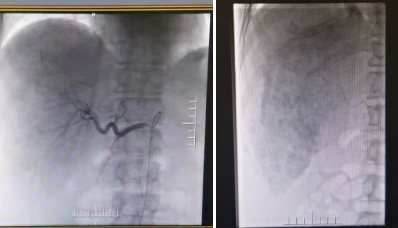

患者李xx,男,58岁;既往有慢性乙肝病史8年余,口服“富马酸替诺福韦二吡呋酯片”抗病毒治疗;患者2018年09月20日确诊为原发性肝癌, 给予肝癌根治术。 2019年6月患者开始出现腹胀乏力等不适,复查发现肝部病灶复发,我院肿瘤科给予2次TACE治疗(肝动脉灌注化疗栓塞术),目前肝部病灶未见明显复发。患者获得了长期的肝脏病灶稳定。

患者开展TACE治疗(肝动脉灌注化疗栓塞术)